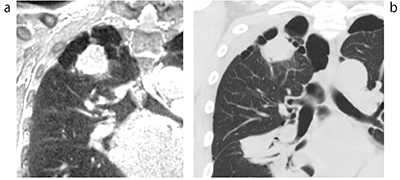

UTEの臨床応用例を示す。肺野組織は,ほかの臓器と比較して空気が支配的であるため,T2/T2*が極端に短く,通常のMR画像では描出が困難である。一方,UTEはTEが1ms以下であるため,肺野の描出が可能となる。図3に,肺野のUTE画像とthin slice CT画像を示す。UTE画像(図3a)においても,CT画像(図3b)同様に扁平上皮癌が右上葉部に認められ,肺気腫と正常部位のコントラストの違いが認められる。

図3 扁平上皮癌の例

UTE画像(a)とthin slice CT画像(b)。UTE撮像条件:(TR:4ms, TE:0.96ms, Flip Angle:6degree/1×1×1mm)。3D FFE UTE(W.I.P),Vantage Titan 3T。

(画像ご提供:神戸大学・大野良治先生)